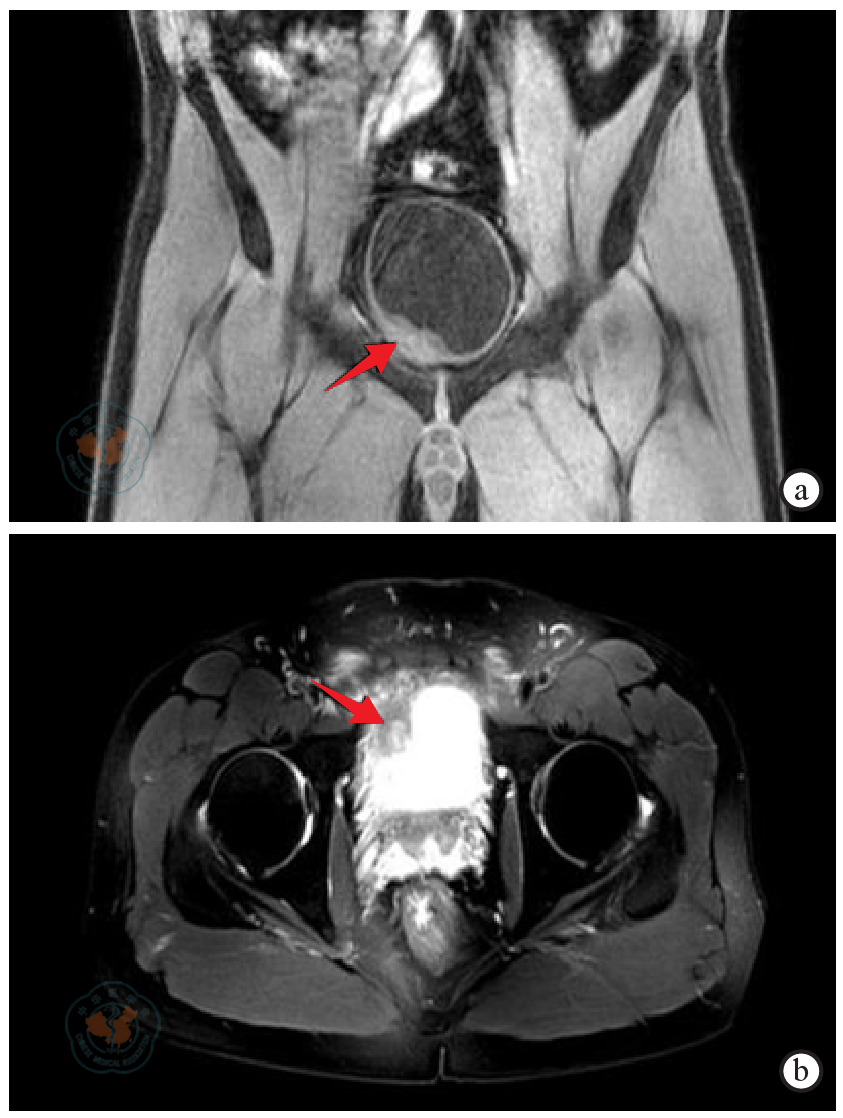

图1 膀胱低级别平滑肌肉瘤患者术前影像注:图a为全腹CT示膀胱右前下壁增厚,可见一软组织肿块影突向腔内,呈宽基底与膀胱壁相连,大小约4.2 cm×1.6 cm×3.3 cm,其内密度欠均(箭头示);图b为盆腔MRI示膀胱右前壁不规则增厚并软组织肿块影,肌层欠连续,可见斑片状高信号影,DWI可见弥散受限,范围约1.4 cm×3.5 cm(箭头示)